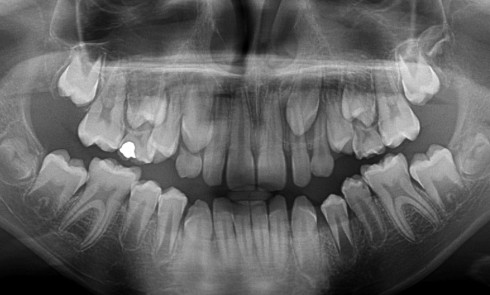

Article réservé à nos abonnés Intérêt de l’avulsion précoce des canines temporaires maxillaires pour une évolution optimisée des canines permanentes